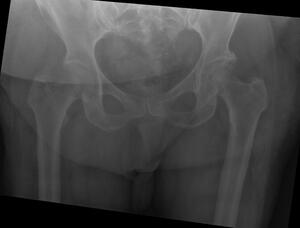

A 64-year-old female with diabetes, hypertension, and dyslipidemia was involved in a motor vehicle accident, resulting in significant injuries. She presented to the Emergency Department via Medivac and underwent a comprehensive trauma assessment. Orthopedic evaluations reveal a fractures dislocation of the left acetabulum with a posterior wall fracture and a femoral head fracture (Figure 1. Figure 2, Figure 3). Additionally, a minimally displaced fractures of the left tibial plafond was identified. Due to the complexity of her injuries and considering her age, a surgical plan was formulated for fixations of the acetabular and femoral head fractures, along with total hip replacements on the left side, and fixations of the tibial plafond fractures. After induction of general anesthesia and regional block, the patient was positioned in lateral decubitus for the hip procedures. Utilizing the Kocher-Langenbeck approach, the posterior wall fracture was stabilized with lag screws and a buttress plate (Figure 4A, 4B). The hip was then dislocated, the femoral neck cut, and the acetabulum reamed. A Stryker Trident cup size 46 was inserted for a press-fit, augmented with three screws, and a metal liner for dual mobility was added. Subsequently, the femur was broached, and an Accolade stem size 2 with a double head was implanted, ensuring excellent stability and appropriate legs length (Figure 4C). The operation concluded with thorough irrigation and closure in layers. The patient was then repositioned supine to address the tibial plafond fracture, which was stabilized with a single medial plate, followed by application of a dry dressing and a below-knee backslabs. Postoperatively, the patient experienced mild pain but was otherwise stable. Dressings on the left hip and ankle were intact, with ankle motion preserved and a palpable dorsalis pedis pulse. She began mobilization with physiotherapy from day one and showed no active complaints throughout her recovery, proceeding smoothly until discharge (Figure 5).